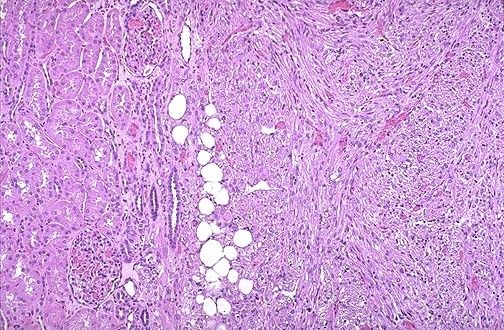

| Angiomiolipoma |

Image:

Renal115 (image/jpeg)